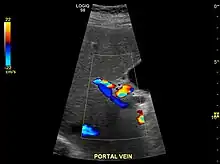

Hepatofugal (non-forward) flow in portal vein

Imaging

Ultrasound is routinely used in the evaluation of cirrhosis.[35] It may show a small and shrunken liver in advanced disease. On ultrasound, there is increased echogenicity with irregular appearing areas.[52] Other suggestive findings are an enlarged caudate lobe, widening of the fissures and enlargement of the spleen.[53] An enlarged spleen, which normally measures less than 11–12 cm (4.3–4.7 in) in adults, may suggest underlying portal hypertension.[54] Ultrasound may also screen for hepatocellular carcinoma and portal hypertension.[35] This is done by assessing flow in the hepatic vein.[55] An increased portal vein pulsatility may be seen. However, this may be a sign of elevated right atrial pressure.[56] Portal vein pulsatility are usually measured by a pulsatility indices (PI).[55] A number above a certain values indicates cirrhosis (see table below).